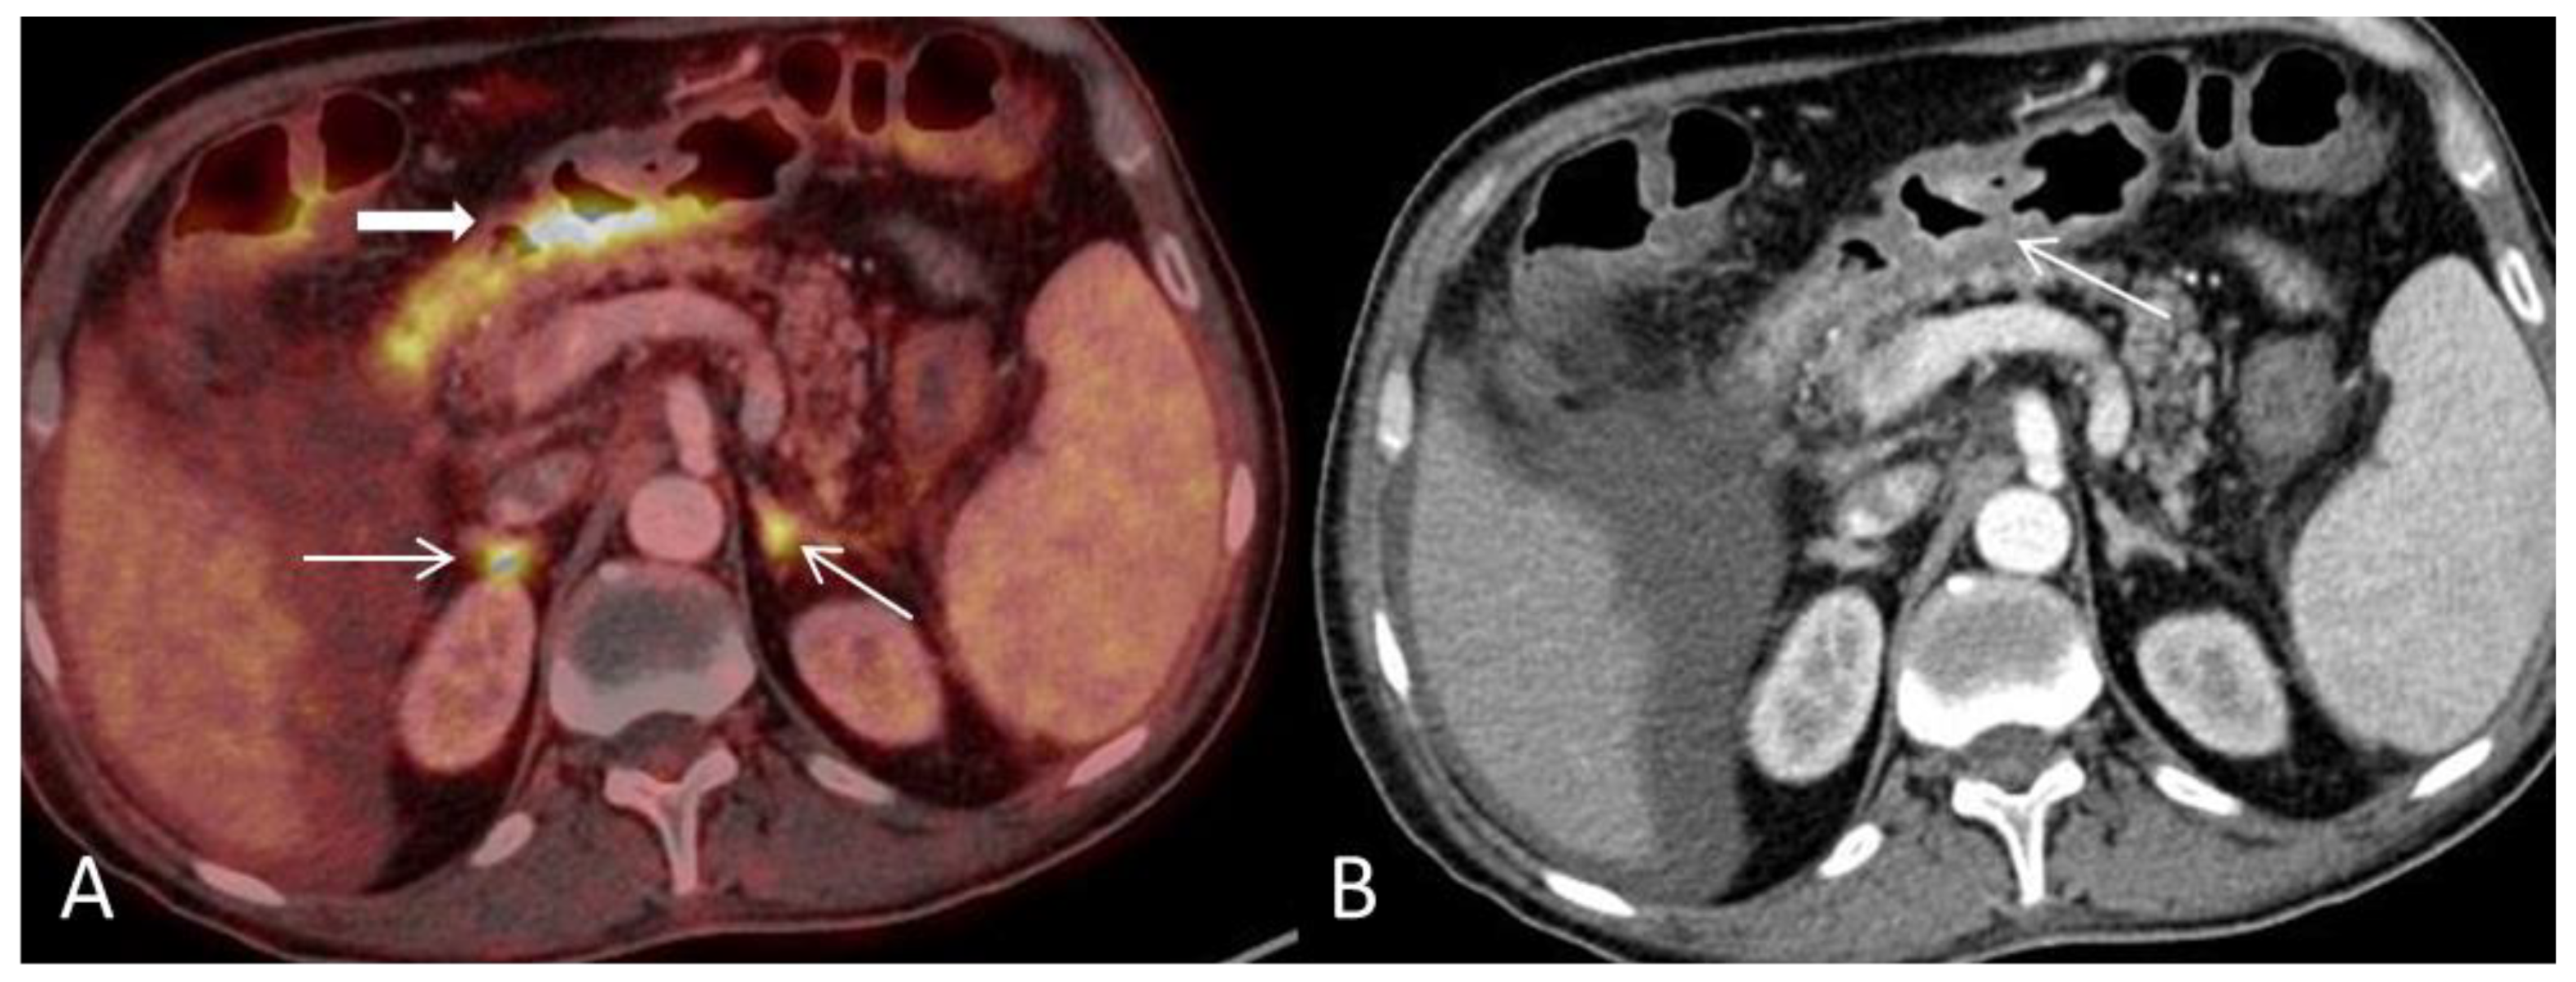

(A) An 18F-FDG PET/CT, with intravenous and oral contrast enhancement, was performed in a 50-year-old man 93 days post autologous SCT for relapse of Hodgkin’s lymphoma. The PET maximum intensity projection (MIP) image shows discontinuous pathological FDG-uptake throughout the GIT extending from the upper esophagus to the anal canal involving the cardia region, ventricle, and segments of the small-and large bowel including the rectum. The PET findings are consistent with an inflammatory response with normal physiological FDG-uptake in unaffected segments of the GIT. At the time of scanning, the patient had severe diarrhea, fever, nausea and reported weight loss but no skin lesions. The clinical presentation with non-specific symptoms and and that the patient was a recipient of autologous SCT rendered infection as a probable diagnosis. However, repeated blood and stools tests for bacterial, common viral and fungal agents were negative. Diagnosis was based on rectal biopsies that showed epithelial cell apoptosis indicative of GVHD according to previously described criteria [1]. No infectious agents were present. Despite intensive treatment the patient succumbed due to complications following sepsis. (B) Normal 18F-FDG PET/CT in the same patient performed immediately post-autologous SCT. Amid the two scans it is evident that the spleen has increased in size resulting in splenomegaly (A). Splenomegaly has previously been described as an extra intestinal finding in acute GVHD-GIT [2]. Clinically, GVHD is divided into acute or chronic GVDH with acute GVHD developing within the first 100 days post-SCT and chronic GVHD as occurring beyond the first 3 months [3]. GVHD is a leading cause of morbidity and mortality in recipients of allogenic SCT. Auto-GVHD has the same clinical and histological presentation as allo-GVHD but is often observed as milder, self-limited and less frequent [4,5,6]. The standard treatment of acute GVHD is steroids, however, acute auto-GVHD can often resolve without treatment, although, fatal cases have been reported [4,5,6,7]. The primary affected organs are the skin, liver and GIT [8], if all three organs are involved diagnosis could be made on clinical grounds alone. Isolated GVHD-GIT is much more challenging to diagnose due its often non-specific symptoms such as abdominal cramping, nausea and vomiting, voluminous and often bloody diarrhea and fever that in the setting of post-HSCT could be treatment related or infectious. 18F-FDG PET/CT has been proposed as a non-invasive imaging modality in assessing intestinal GVHD, map its localization and monitor treatment response [9,10,11]. Here, we present an 18F-FDG PET/CT scan where many of the most common reported CT and PET/CT features of GIT-GVHD were present [2,9]. Common PET/CT features of bowel inflammation are non-specific and could represent inflammatory bowel disease such as enterocolitis, Mb Crohn or ulcerative colitis the discontinuous pattern and extent (from esophagus to rectum) of GIT involvement led to us to suggest GVHD as a differential diagnosis. However, caution must be taken for false positive results with/or without accompanied morphological changes. A previous study reported false-positive results for acute-GVHD related to daily metformin treatment [10]. Other pathological underlying causes for pathological FDG-uptake in the GIT must be considered, such as malignancy, benign neoplasms or inflammation due to esophagitis or gastritis [12]. Furthermore, physiological FDG-uptake within the normal GIT is highly variable and findings should be interpreted with care [12]. In this case, many of the possible differential diagnosis could be excluded due to a recently previous FDG-PET/CT scan (B) available for comparison which rendered a new malignancy as improbable and the patient had no medical history of inflammatory bowel disease or metformin treated diabetes.